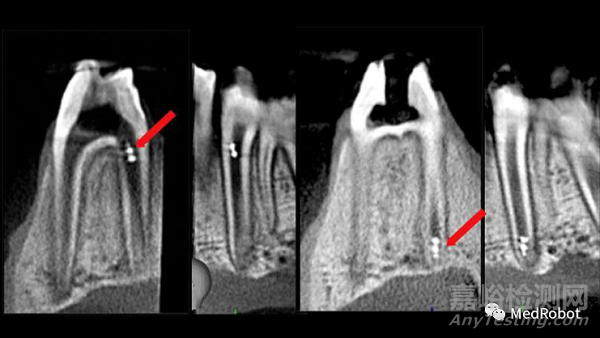

▲紅色箭頭所指示的磁制動3D微型機(jī)器人被精確控制,

以達(dá)到根管的頂端區(qū)域

(圖源:賓夕法尼亞大學(xué))

此外,研究小組展示了使用現(xiàn)有的成像技術(shù)(如口內(nèi)掃描儀,牙科X射線和錐形束計(jì)算機(jī)斷層掃描)實(shí)時跟蹤微型機(jī)器人的獨(dú)特能力,這些技術(shù)能夠在完整的牙管中定位螺旋體。